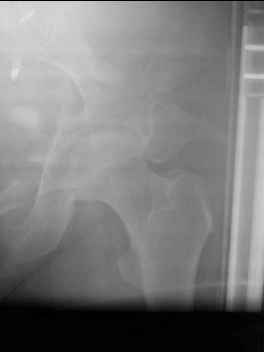

I'm posting this case on behalf of Dr. Pedro Caba, he is unable to post but able to read. 41 yo female , fall from 10 meters five days ago. Hemodynamically unstable on admission treated by angio and embolization and skeletal traction, with no external support. No associated injuries. Based on CT scan the pt has a both column fracture with conminuted dome and displaced anterior column and a sacral Denis 1 fracture with a displaced left ala. I think the best approach for the acetabular fracture is ilioinguinal with Smith-Petersen extension but don't know exactly the sequence . Will you start with the sacral fracture? Which technique? Thanks in advance Pedro Caba Unidad de Trauma Hospital 12 de Octubre Madrid Spain

The sacral pattern alone is quite difficult and seems to be some version of an H-pattern, but I can’t tell from these films.

This complex and displaced sacral injury is likely an H pattern...2 hemipelvic components, an upper sacral component which remains attached to the lumbar spine, and a caudal sacral component...there are typically anterior ring injuries as well...in this patient's example, the left sided acetabulum also has been exploded.

The hemipelvic components' displacements depend on their instability...this patient's left side seems to be the worst.